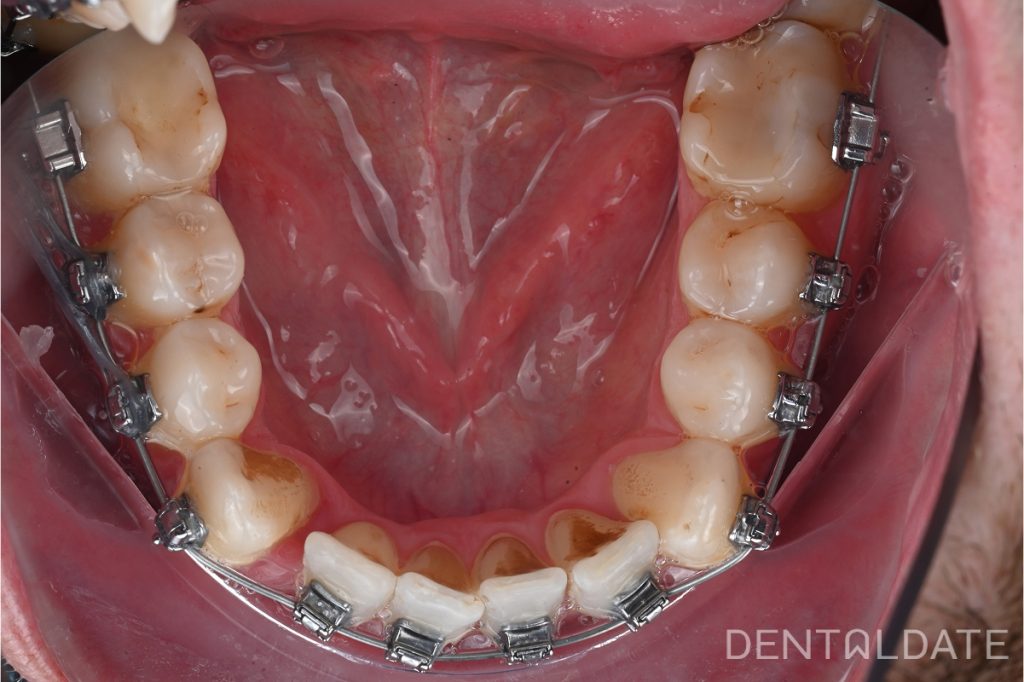

Now in the photo is the work of a DentalDate specialist.

Just one month after correct placement, the results are clear: the necessary space has been created, and the dental arch has become wider and more symmetrical.